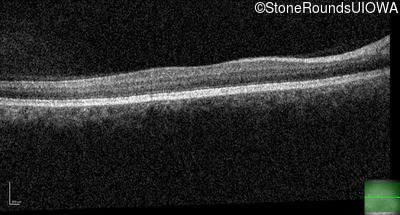

Congenital Stationary Synaptic Dysfunction (IA2g)

Congenital Stationary Synaptic Dysfunction (IA2g)

| Congenital Stationary Synaptic Dysfunction | CABP4 | Arg49Stop CGA>TGA | IVS1+1 G>T | AR |